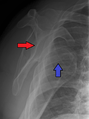

Lightbulb sign indicative of posterior shoulder dislocation shown on the left. On the right, the same shoulder after reduction.